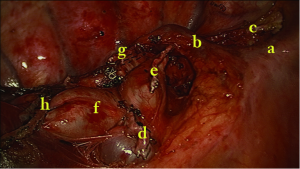

Mediastinal lymph node (MLN) dissection

Move the operating table anteriorly. Systematic lymph node dissection using en bloc excision, instead of systematic sampling, is applied for the removal of 2, 4, 7, 8 and 9 MLNs. We use the same method as in the biportal approach (4). Cut open mediastinal pleura by a “∩” shaped incision for 7th, a “⊿” above azygos vein and “– ” beneath azygos vein for 2th and 4th which greatly simplify the en bloc MLNs dissection (Figures 7,8,9).